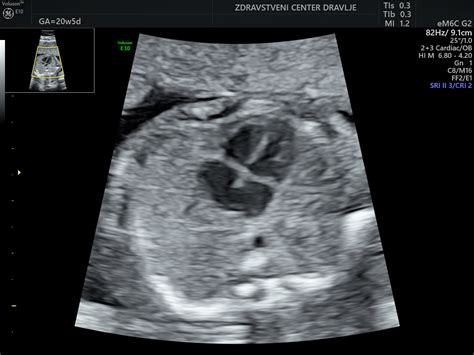

Večina nosečnosti vključuje vsaj dva rutinska ultrazvočna pregleda. Prvi je ultrazvok v zgodnji nosečnosti (od 6. do 10. tedna), ki potrdi trajanje nosečnosti, določi njeno mesto (v ali izven maternice), vrsto (eno- ali večplodna) ter preveri plodov srčni utrip. Drugi pomemben pregled je morfološka ocena ploda, ki poteka med 20. in 24. tednom nosečnosti. Ta daljša ultrazvočna preiskava omogoča podroben pregled razvoja plodovih organov, preverjanje lege in kakovosti posteljice, popkovnice, količine plodovnice ter pretoka krvi skozi žile. V tem obdobju je, če je lega ploda ugodna, mogoče določiti tudi spol otroka.